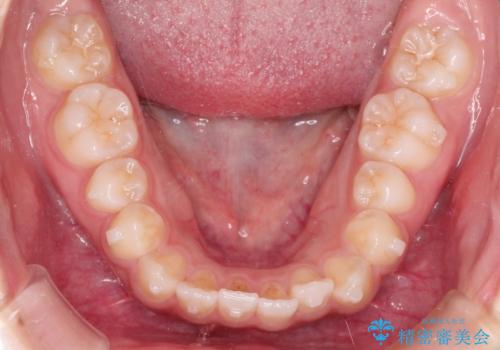

インビザライン 前歯のがたつきを目立たず矯正

- 前歯のがたつきが気になるとのことで来院されました。

インビザラインにて治療を行いました。

わずかに歯と歯の間に隙間を作り、歯列矯正を行いました。

マウスピースをしっかりと使用していただけたので、スムーズに治療を終了することができました。